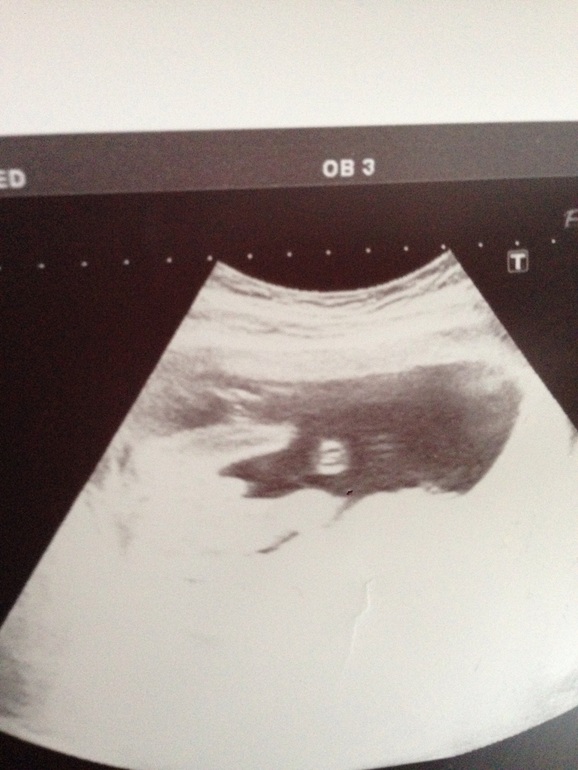

Я сразу увидела где там что на фотке)))))) поздравляю, здОрово!!!мне через 2 недели на УЗИ, надеюсь, что между ножек не увидим ничего

Если бы вы не написали, то не разобралась бы глядя на фото, что изображено

).